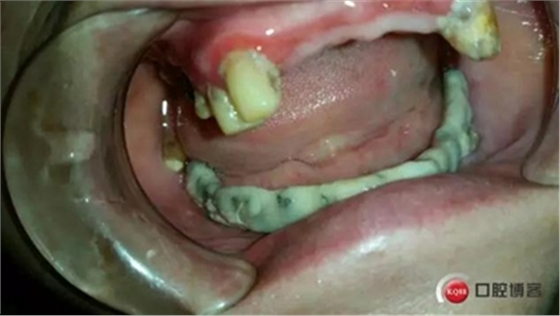

取牙模